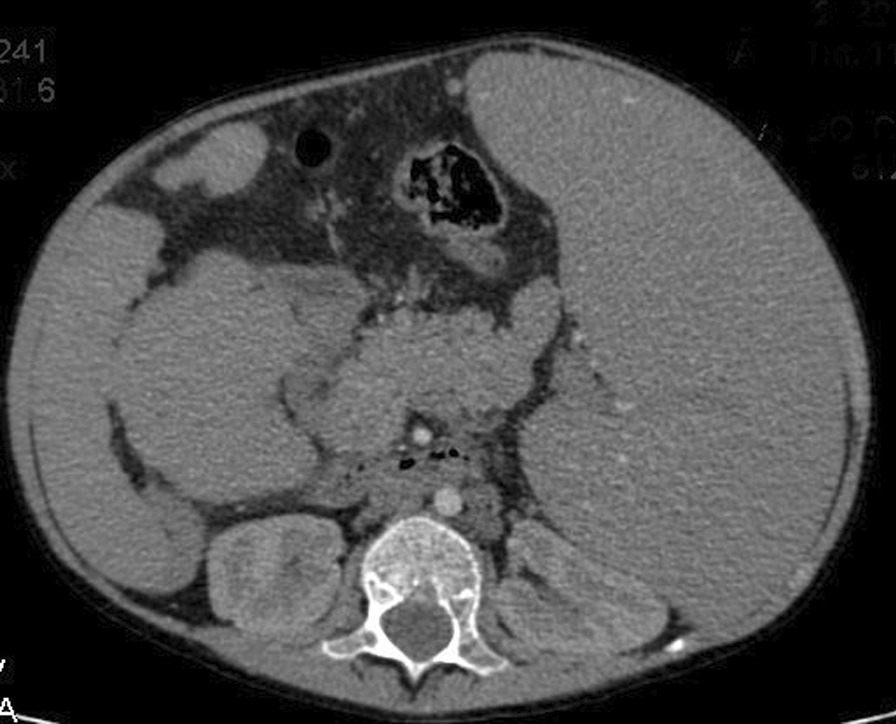

The investigations started with laboratory tests (Table 1). Complete blood count (CBC) and blood smear showed pancytopenia. However, the bone marrow biopsy was normal. Esophagoscopy used to be done every 3 months for the past year. In the last one, fourth-grade non-bleeding varices were found. The abdominal ultrasound demonstrated multiple septated cystic formations within the liver containing turbid liquid. It also showed splenomegaly that measured 18 cm. The portal vein diameter was 7 mm, and the splenic vein measured 6 mm. Abdominal computed tomography (CT) scan with contrast showed intrahepatic cystic formations in the right and left lobes (Fig. 2). The greatest one measured 7 × 9.5 cm. These cysts have a tubular appearance and connect to the bile ducts inside the liver, which is consistent with Caroli disease. The liver borders are irregular with a cirrhotic look. There is a generalized enlargement of the spleen measuring 17 cm (Fig. 3). The kidney, the bladder, and the pancreas are normal. The cardiac ultrasound showed a secundum atrial septal defect (ASD) measuring 11 mm with left-to-right shunting and mild right heart dilatation. The pulmonary flow was 1.8 mm/second. Ejection fraction (EF) was 74%. (Fig. 4) In addition, no genetic study was carried out of the patient and her deceased siblings previously. The final diagnosis for the recent condition was splenomegaly with hypersplenism.

Fig. 2.

Abdominal CT scan with contrast showing intrahepatic cystic formations